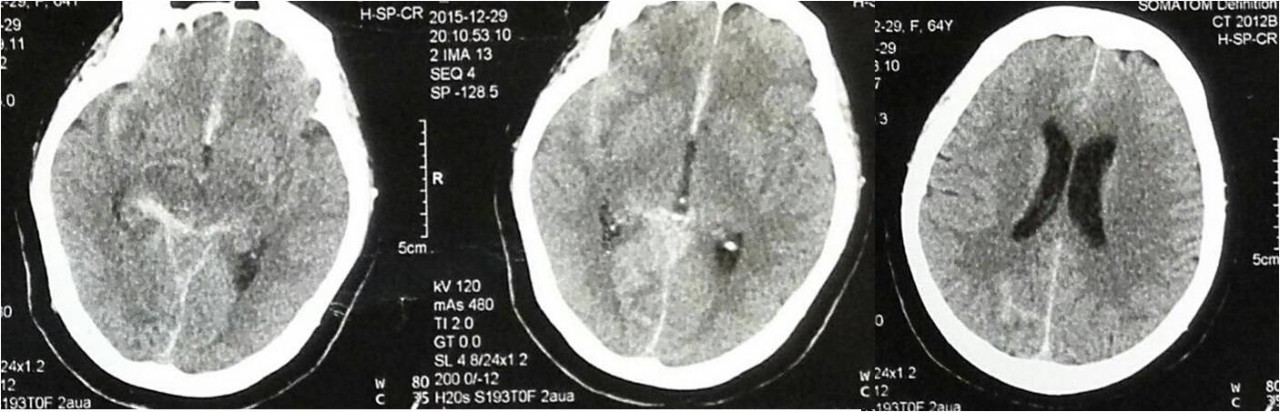

术后即刻复查头颅CT

》术后即可复查头颅CT未见蛛网膜下腔出血。